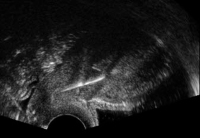

"Selten, aber typisch": Die extrauterine Dislokation des IUD - eine Übersicht

Journal für Gynäkologische Endokrinologie 2012; 6 (2) (Ausgabe für Österreich): 12-17 Journal für Gynäkologische Endokrinologie 2012; 6 (2) (Ausgabe für Schweiz): 14-19 Volltext (PDF) Summary Praxisrelevanz Abbildungen